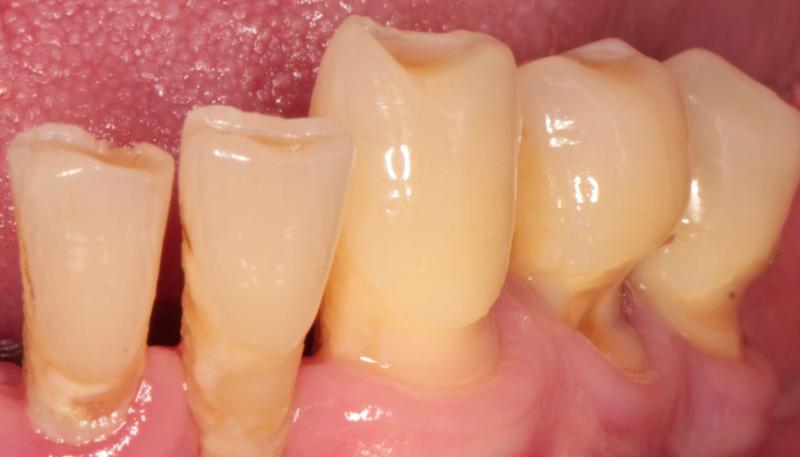

Pacjenci z problemem odsłoniętych szyjek zębowych z pewnością zasługują na naszą uwagę. Najczęściej z tym kłopotem zmagają się osoby w średnim wieku, jednak nie tylko one — również młodsze osoby mogą odczuwać nadwrażliwość i ból przy spożywaniu zimnych lub gorących potraw. Odsłonięte szyjki zębowe stają się nie tylko estetycznym problemem, ale także poważnym wyzwaniem zdrowotnym, które może prowadzić do próchnicy oraz obniżenia komfortu życia. Dlatego w momencie, gdy odczuwasz ból podczas picia ulubionego napoju, warto pomyśleć o wizycie u stomatologa!

Objawami takich kłopotów często są nieprzyjemne reakcje na ciepło, zimno oraz kwaśne potrawy. Można to porównać do włosów — wszyscy możemy je mieć, ale ich zaniedbanie przynosi wiele niedogodności. Odsłonięte szyjki zębowe psują estetykę i prowadzą do wycofywania się dziąseł, co jest prosta drogą do poważniejszych problemów. Właśnie dlatego nie należy bagatelizować tego stanu — im szybciej podejmiemy działania, tym lepsze osiągniemy rezultaty!

W grupie ryzyka znajdują się osoby z nieprawidłową higieną jamy ustnej, które używają twardych szczoteczek lub traktują zęby jak świeżo nabyte buty, czyszcząc je zbyt intensywnie. Ponadto pacjenci z chorobami dziąseł, wadami zgryzu czy bruksizmem, czyli znanym nawykiem zgrzytania zębami w nocy, również mogą borykać się z problemem odsłoniętych szyjek. Dodatkowo problem ten dotyka osoby, które nie mają czasu na regularne wizyty u dentysty. Warto również pamiętać, że niekiedy to geny wpływają na nasze zdrowie — niektóre osoby po prostu posiadają większe predyspozycje do recesji dziąseł, co sprawia, że są bardziej podatne na te dolegliwości.

Odsłonięte szyjki zębowe to temat, który wywołuje więcej uśmiechu niż strachu, jednak trzeba podchodzić do niego ostrożnie! Gdy szyjki zaczynają się odsłaniać, jakby chciały zasłonić się wstydem, jest to wyraźny sygnał, że coś jest nie tak. Często zaniedbana higiena jamy ustnej staje się przyczyną odsłonięcia tych delikatnych części zębów. Każdy z nas zna to uczucie, gdy intensywne „szorowanie zębów” zamienia się w zmagania z kamieniem nazębnym. Można to porównać do mycia samochodu za pomocą twardej szczotki, podczas gdy delikatna gąbka zrobiłaby znacznie lepszą robotę. Efekt? Zamiast błyszczeć, auto staje się jeszcze bardziej zakurzone! Z podobnym problemem borykają się nasze zęby – zbyt agresywne ruchy to prosta droga do kłopotów.

Mówiąc o problemach, nie możemy zapomnieć o nadwrażliwości zębów. Kto z nas nie doświadczył tego dramatycznego momentu, gdy przy picu gorącej herbaty ząbkuje nas tak, jakby miał ostry jak brzytwa? Nadwrażliwość to nic innego jak głośny krzyk protestu zębów, które domagają się: „Zróbcie coś z tymi odsłoniętymi szyjkami!”. Co więcej, odkryte części zębów stają się paradoksalnie bardziej podatne na próchnicę, co prowadzi nas do nieuchronnych wizyt u dentysty. Gdy dodatkowo ból pojawia się przy jedzeniu kwaśnych czy słodkich potraw, nie należy czekać – czas udać się do specjalisty!